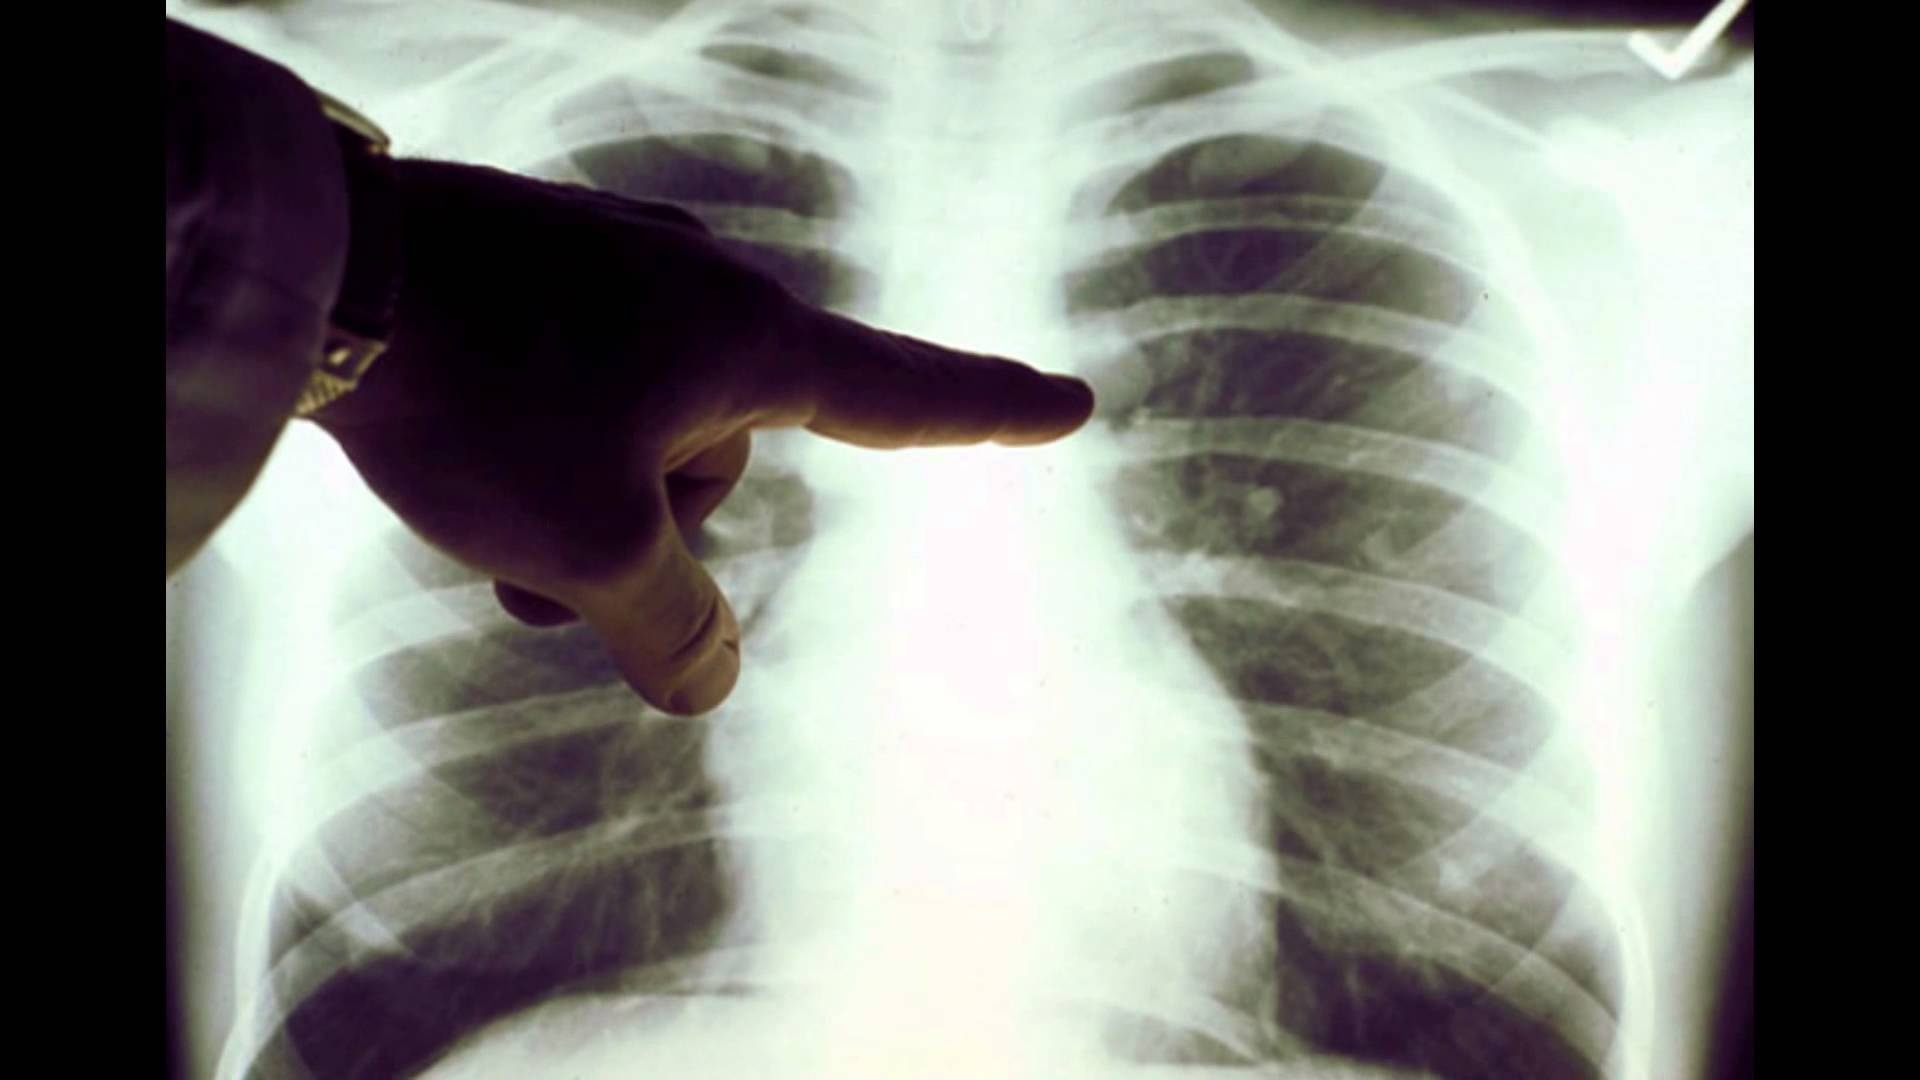

Có thể chẩn đoán ung thư phổi theo phương pháp nào? Ảnh: Lungcancer.

Khi bệnh nhân nhận thấy cơ thể có các triệu chứng của bệnh ung thư phổi, nên đến bệnh viện để chụp X-quang và thực hiện các xét nghiệm hình ảnh, xét nghiệm đờm. Khi bác sĩ xác định được dấu hiệu bệnh ung thư phổi qua bản chụp X-quang, bệnh nhân sẽ được tiến hành sinh thiết phổi. |